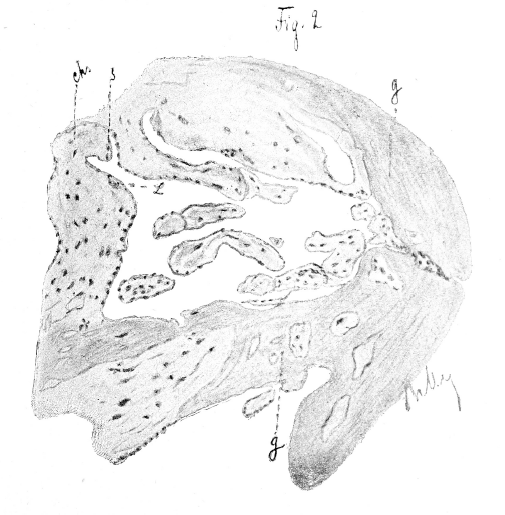

Рис.2

Рис. 2. Hartnack. Ocul. 2, Obj. 8. II случай: ворсинки съ децидуальной тканью. Ch—ворсинки хоріона съ syncytium (s) и клѣтками Langhans's. (L), g—гомогенная масса замѣнившая клѣтки deciduae foetalis.